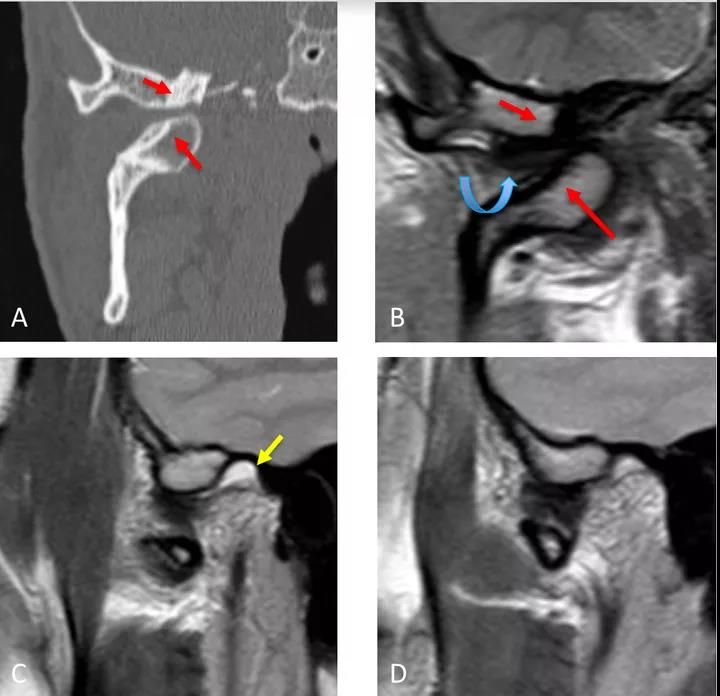

病例二:顳下頜關(guān)節(jié)脫位

冠狀面CT圖(A)和冠狀面PDWI圖(閉口)(B):顯示由于先前骨折導(dǎo)致的下頜髁突內(nèi)側(cè)移位的顳下頜關(guān)節(jié)脫位,與骨折畸形愈合、前上髁和后顳嵴硬化(紅色箭頭)相關(guān)。關(guān)節(jié)盤(pán)位于下頜骨髁突和顳突之間,失去正常的形態(tài)(彎曲箭頭)。

矢狀位T2WI圖(閉口)(C):顯示正常位置的下頜骨髁突及關(guān)節(jié)積液(黃色箭頭)。

矢狀位PDWI圖(開(kāi)口)(D)顯示髁突明顯偏移。